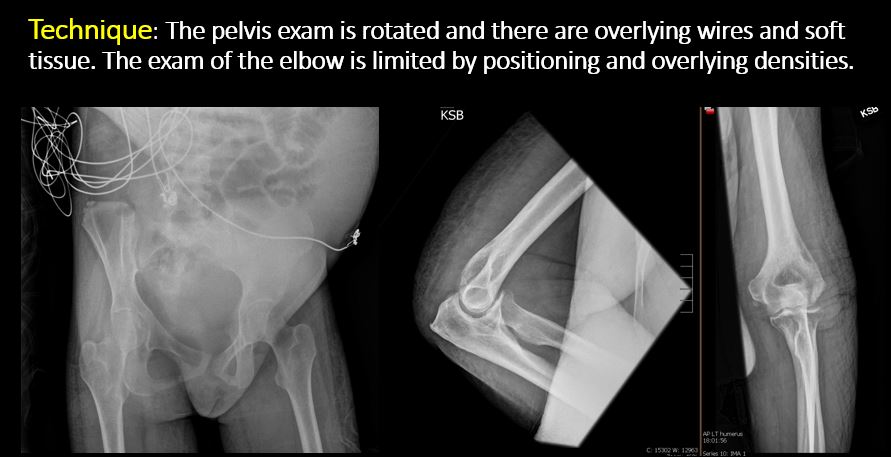

| Technique | Correct Answer | Your Answer |

|---|---|---|

|

The exam is over or under penetrated. |

No | NA |

The exam is limited by overlying structures or soft tissues, body habitus, patient positioning, support devices, or motion. |